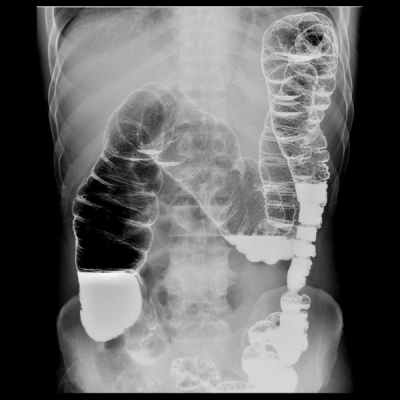

На контрастном снимке видно, что кардиа, свод и тело желудка образуют нисходящую часть тени, а пилорическая часть желудка — восходящую часть тени (рис. 126, 127). Соотношения нисходящей и восходящей частей тени желудка у разных людей неодинаковы; можно наблюдать три основных формы и положения желудка.

1. Желудок в форме рога (рис. 128). Тело желудка расположено почти поперек, постепенно суживаясь к пилорической части. Привратник лежит вправо от правого края позвоночного столба и является самой низкой точкой желудка. Вследствие этого угол между нисходящей и восходящей частями желудка отсутствует. Весь желудок расположен почти поперечно.

2. Желудок в форме крючка (рис. 129). Нисходящая часть желудка спускается косо или почти отвесно вниз. Восходящая часть расположена косо — снизу вверх и направо. Привратник лежит у правого края позвоночного столба. Между восходящей и нисходящей частями образуется угол (incisura angularis), несколько меньший прямого. Общее положение желудка косое.

3. Желудок в форме чулка, или удлиненный желудок. Он похож на предыдущий («крючок»), но имеет некоторые отличия: как говорит само название, нисходящая часть его более удлинена и спускается вертикально; восходящая часть поднимается вверх круче, чем у желудка в форме крючка. Угол, образуемый малой кривизной, более острый (30 — 40°). Весь желудок расположен влево от срединной линии и лишь незначительно переходит за нее. Общее положение желудка вертикальное.

Таким образом, между формой и положением желудка отмечается корреляция: желудок в форме рога имеет чаще поперечное положение, желудок в форме крючка — косое, удлиненный желудок — вертикальное положение.

Форма желудка в значительной мере связана с типом телосложения. У людей брахиморфного типа с коротким и широким туловищем часто встречается желудок в форме рога. Желудок расположен поперечно, высоко, так что самая низкая часть его находится на 4 — 5 см выше линии, соединяющей подвздошные гребни, — linea biiliaca.

У людей долихоморфного типа телосложения с туловищем длинным и узким чаще встречается удлиненный желудок с вертикальным положением. При этом почти весь желудок лежит слева от позвоночного столба и располагается низко, так что привратник проецируется на позвоночнике, а нижняя граница желудка опускается несколько ниже linea biiliaca.

У людей переходного (между двумя крайними) типа телосложения наблюдается форма желудка в виде крючка (рис. 130). Положение желудка косое и среднее по высоте; нижняя граница желудка — на уровне linea biiliaca. Эти форма и положение наиболее распространены.